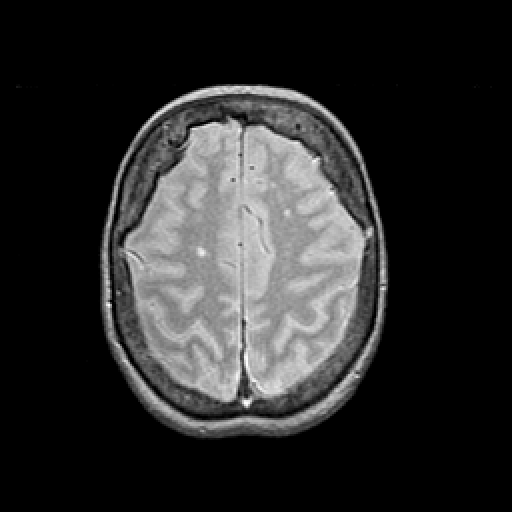

Proton density-weighted structural MR: Slice 40

Slice 40